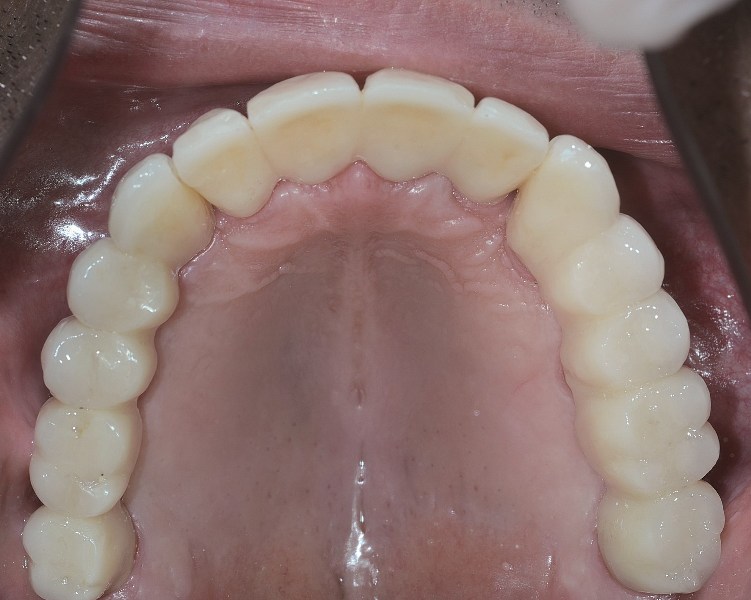

Pełna rekonstrukcja uzębienia jest jedną z najtrudniejszych procedur w stomatologii. Jeżeli odbudowa protetyczna uzębienia obejmuje także własne zęby pacjenta, to możemy wykorzystać korony, mosty i implanty występujące pojedynczo lub połączone w mosty. Pełną rekonstrukcję zaczynamy od wstępnej analizy jamy ustnej, modeli pacjenta stworzonych na podstawie wycisku, zdjęć rtg oraz tomografii. Na podstawie tych informacji wykonujemy projekt przyszłego uzębienia. Dalszy przebieg leczenia jest uzależniony od tego, jakie procedury należy wykonać, zanim możliwa będzie implantacja. Po wszczepieniu implantów następuje etap uzupełnień tymczasowych/próbnych, na podstawie których pacjent może ocenić estetykę i wygodę przyszłych uzupełnień stałych. Pacjent ma szansę zgłosić swoje uwagi do zaproponowanych uzupełnień stałych i uzyskać efekt końcowy, który go całkowicie ustatysfakcjonuje

Choć pojęcie kosztów jest względne i nie dla wszystkich pierwszorzędne, to faktycznie trzeba mieć świadomość, że implanty kosztują dość dużo. Jednak warto spojrzeć na ten rodzaj leczenia długofalowo. W porównaniu z innymi sposobami leczenia ten początkowo wysoki koszt może okazać się konkurencyjny, zwłaszcza jeśli uwzględnimy uzyskane efekty implantacji w postaci estetyki i długotrwałości uzębienia. Istotną zaletą implantacji jest także to, że nie narusza ona sąsiednich zębów, nie działa destrukcyjnie na stan posiadanego uzębienia naturalnego. Implanty wraz z wykonanymi na nich odbudowami protetycznymi znacząco poprawiają warunki zgryzowe pacjenta, co oznacza między innymi lepsze trawienie i eliminację problemów związanych z układem pokarmowym. Wreszcie, i tu wracamy do punktu wyjścia naszej rozmowy, uzyskany w wyniku leczenia estetyczny uśmiech przyczynia się do wzrostu pewności siebie, poprawy samopoczucia, zwalczenia kompleksów. Krótko mówiąc – implanty zmieniają życie na lepsze.